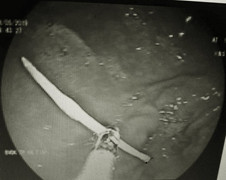

Người đàn ông lâm tình trạng đau bụng âm ỉ, đau nhiều không rõ nguyên nhân trong một tuần do xương cá mắc kẹt ở hành tá tràng.